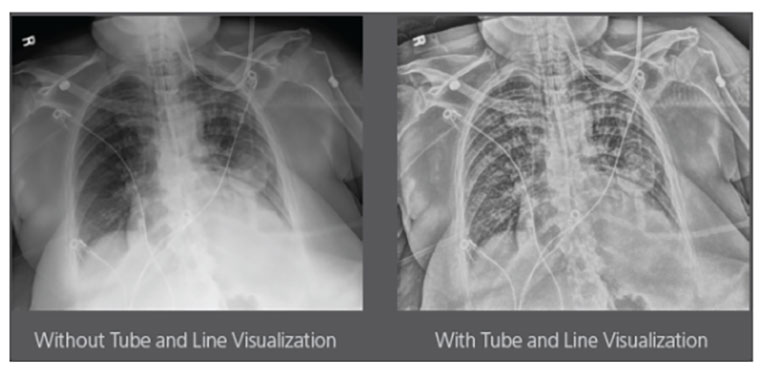

Our Carestream Focus HD 35/43 Retrofit Detectors, powered by Image Suite Software, are an ideal solution to step up to full digital X-ray for customers who simply cannot compromise on image quality. It seamlessly integrates into existing setups, bringing the power of full digital X-ray with minimal disruption and maximum clarity, along with the following benefits: